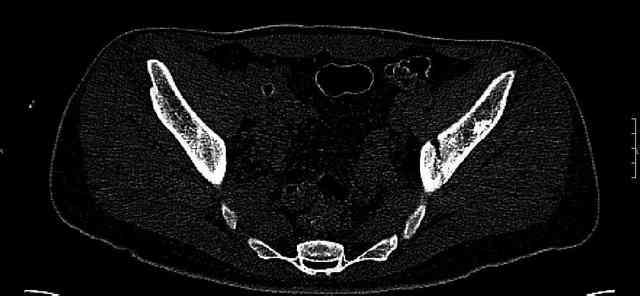

While not claiming to have the best 3D brain around, it appears to me from the limited images available, that the caudal segment is stable from the symphysis to the SI joint on the fracture side. I would love to see the rest of the transverse CT images to see where the fracture line actually exits posteriorly on both the inner and outer tables of the ilium. In my hands,

Some more images. Does it help to guess which part of the acetabulum is displaced?

Normal appearing SI joints and a healed posterior column limb... my bet's on caudal segment displacement.